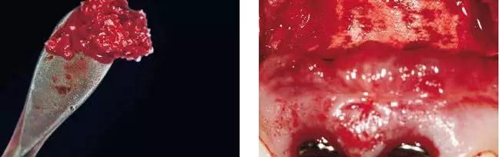

圖6、從磨牙后區(qū)用環(huán)形鉆獲取自體骨,并將其放置在種植體的表面。Geistlich Bio-Oss®骨顆?;旌涎悍胖迷谧泽w骨的外側(cè),防止自體骨的早期吸收。植骨可以穩(wěn)定軟組織外形。

圖10、為了避免對(duì)植骨區(qū)的干擾,外側(cè)覆蓋Geistlich Bio-Gide®膠原膜。

圖11、穿黏膜愈合1周后,牙齦外形良好。